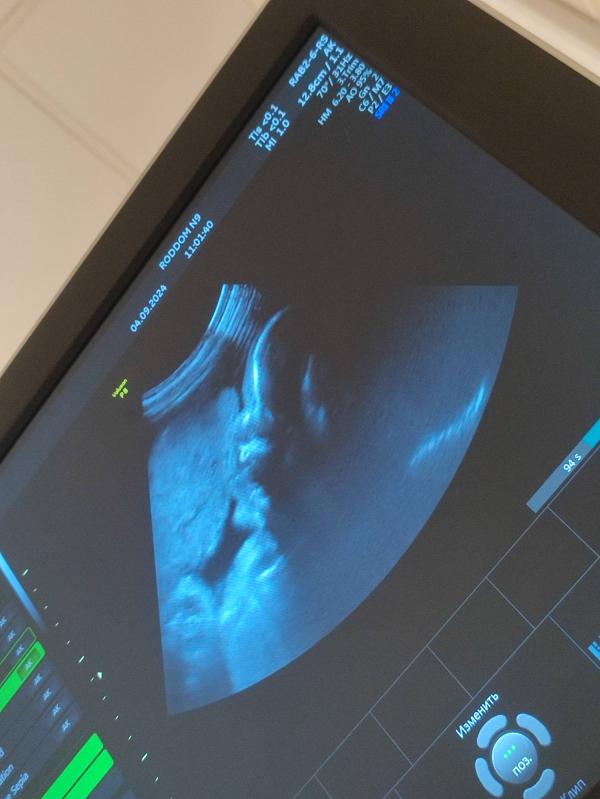

Поднялась я на дневной стационар посмотрели направление, отправили вниз в роддом (где приёмный покой) на узи + сдать мочу и сказали, что если белок будет 0.3, то они меня возьмут, если больше 0.3, то в стационар лягу. Спустилась долго сидела в очереди на узи (девушек было много) в итоге подошла моя очередь посмотрели малыша у него всё хорошо, кровотоки хорошие, весит он 1 кг 826 грамм, лежит в головном предлежании, пинается в правый бок ногами. Почки тоже хорошие, правая увеличина, но мне сказали, что это пройдёт после родов.